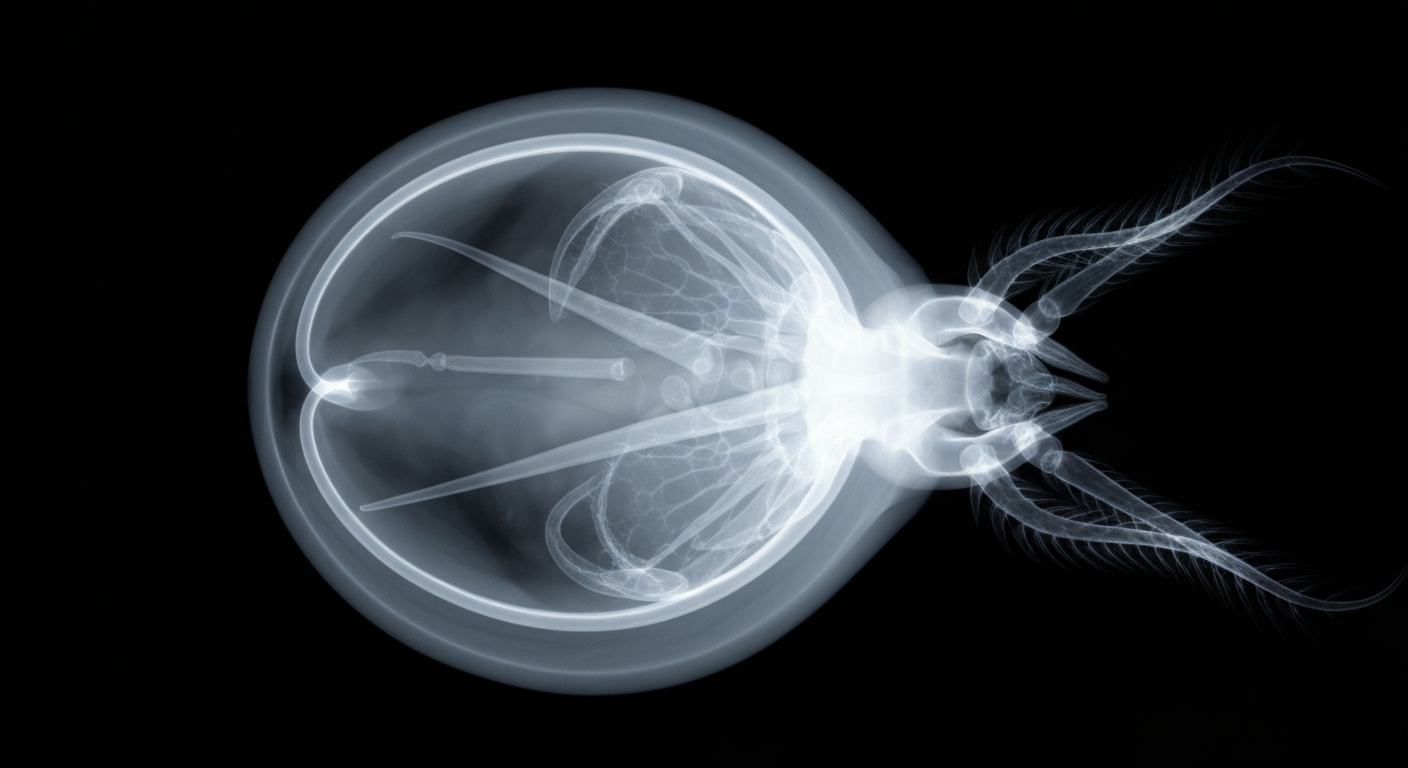

An X-ray view of a tick's anatomy highlights the growing public health threat posed by these disease-carrying insects.NYC TodayAccording to new data from the CDC, tick bites are sending Americans to emergency rooms at the highest rate in nearly a decade. During the second week of April 2026, 71 out of every 100,000 ER visits were for tick bites - more than double the usual average of about 30 per 100,000. The Northeast is seeing the biggest spike, followed by the Midwest, Southeast, West and South Central regions.